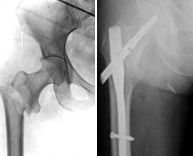

Fracturas de tercio superior del fémur

Las fracturas del tercio superior del fémur, aunque también pueden producirse en pacientes jóvenes, son fracturas más frecuentes en la edad avanzada y debido a mínimos traumatismos a causa de la osteoporosis a este nivel. El enorme espectro de fracturas que existe en esta zona es amplio y por tanto sus tratamientos son distintos.

Los tratamientos conservadores exigen grandes temporadas de encamamiento dada la localización de la lesión por lo que abogamos siempre que sea posible por una cirugía mínimamente invasiva gracias a la cual con pequeñas incisiones se restaura con facilidad la anatomía devolviendola articulación a su rango de movilidad habitual en el menor tiempo posible.